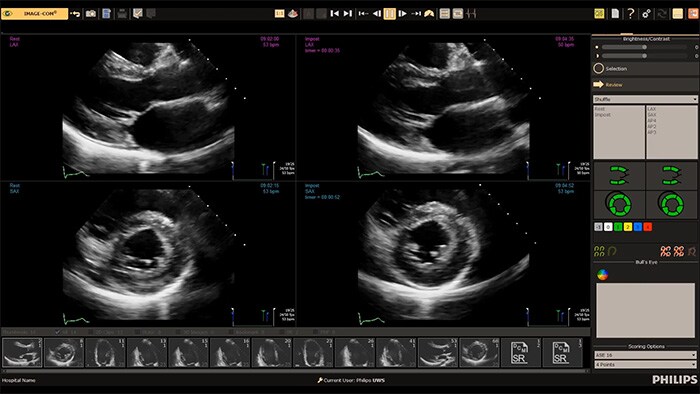

Todo Corazón Importa es el compromiso de Philips de impulsar la excelencia en cardiología, conectando innovación, precisión y confianza para mejorar la experiencia de atención y los resultados clínicos a lo largo de toda la trayectoria del paciente.

Descargue y regístrese en nuestra aplicación Philips CVx Circle y haga parte de la red global de educación contínua con webinars de las últimas tecnologías y avances en cardiología.